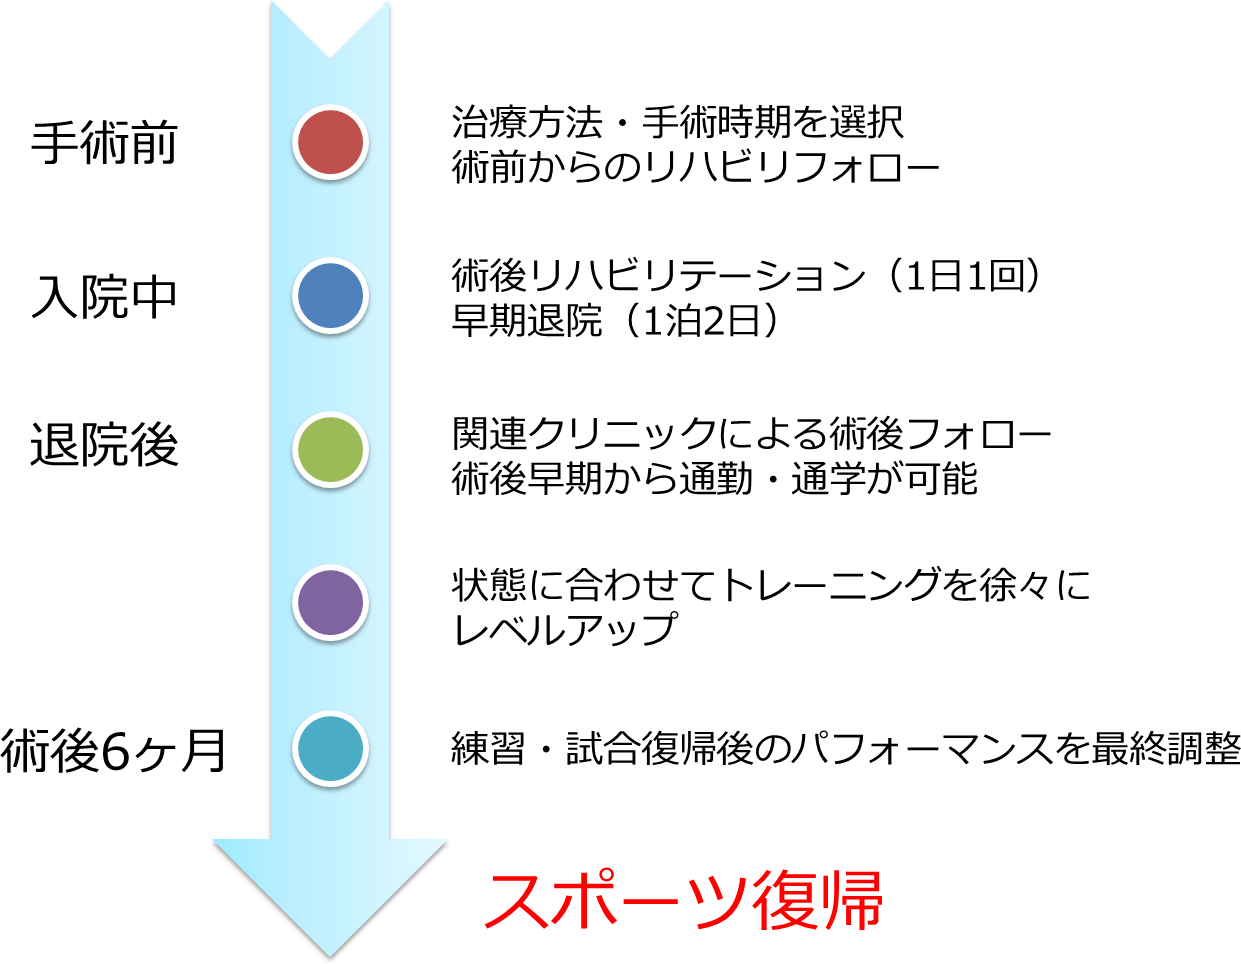

手術前からスポーツ復帰までの流れは?

手術前からスポーツ復帰までの流れは?